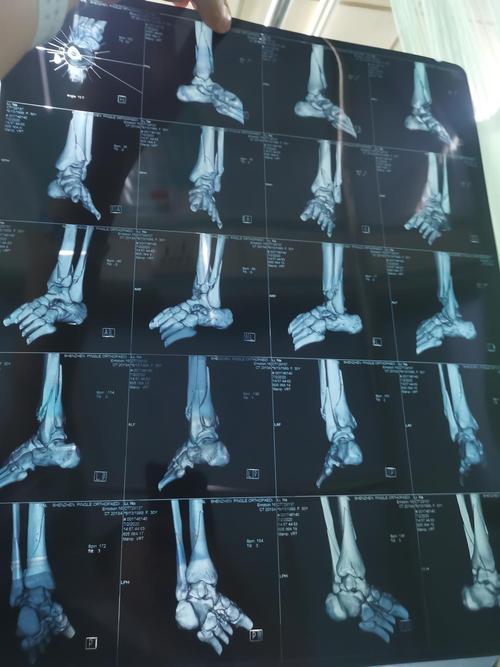

脚ct图片大全骨折,脚踝骨折ct图片清晰

骨折ct胫腓两处骨折 脚踝旋转

脚踝骨折有ct片请各位给点建议

脚踝骨折ct图片清晰

骨折ct图

脚ct片子

胫腓骨骨折